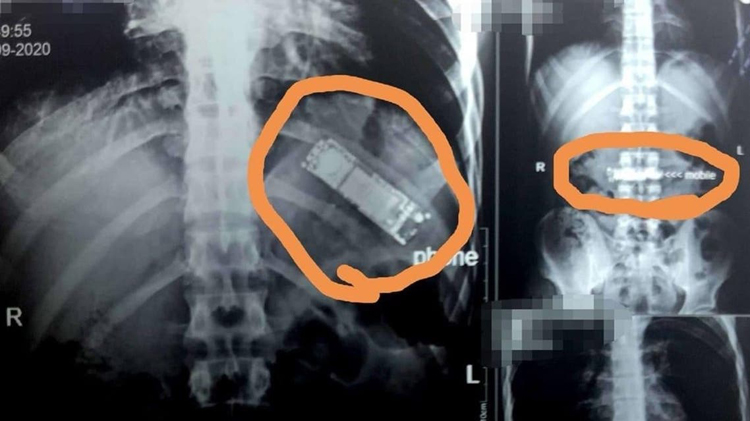

مصری مریض کے پیٹ سے سات ماہ بعد موبائل برآمد

یہ شخص سینے اور پیٹ میں شدید تکلیف کی شکایت لے کر ہسپتال آیا تو اس کا مکمل چیک اپ کیا گیا۔ ایکسرے کرنے کے بعد موبائل فون کی موجودگی کا پتہ چلا۔

دریافت کرنے پر مریض نے بتایا کہ اس نے سات مہینے قبل دوستوں کےکہنے پر یہ موبائل نگل لیا تھا۔ اس کا خیال تھا کہ قے آنے سے موبائل فون واپس باہر نکل آئے گا مگر ایسا نہیں ہوا اور اس نے اہل خانہ سے اس کا ذکر بھی نہیں کیا۔

ہسپتال میں ڈاکٹروں کی ٹیم نے دو گھنٹے طویل اور کامیاب آپریشن کر کے موبائل نکال لیا ہے۔

ڈاکٹر کا کہنا ہے کہ مریض کی قسمت اچھی ہے کہ موبائل کی بیٹری پیٹ میں تحلیل نہیں ہوئی ورنہ بیٹری کے اندر موجود کاربن کے زہرآلود ہونے کے باعث اس کی جان کو خطرہ لاحق ہو سکتا تھا۔